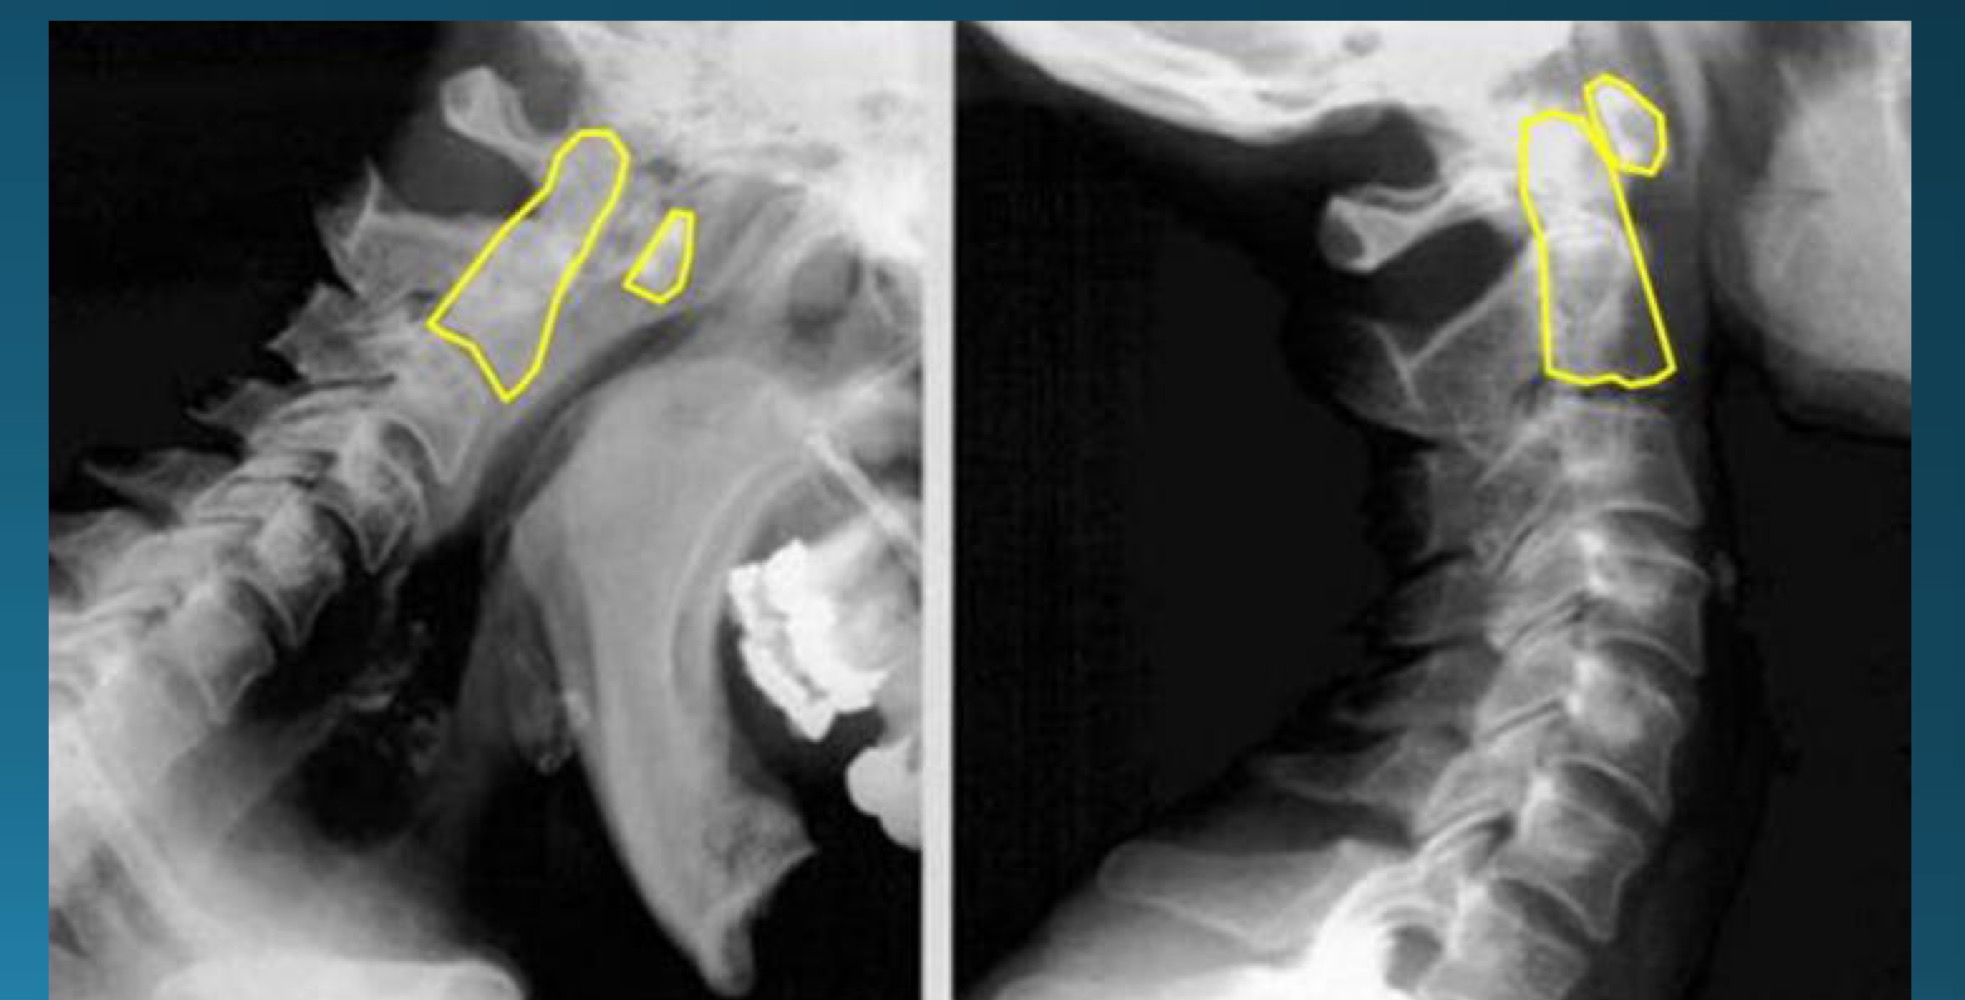

what degenerative joint disease is only found in the cervical spine

uncovertebral joint arthrosis

what are the findings in this image?

what do you call the radiographic feature commonly seen in uncovertebral joint arthrosis

pseudofracture

facet arthrosis